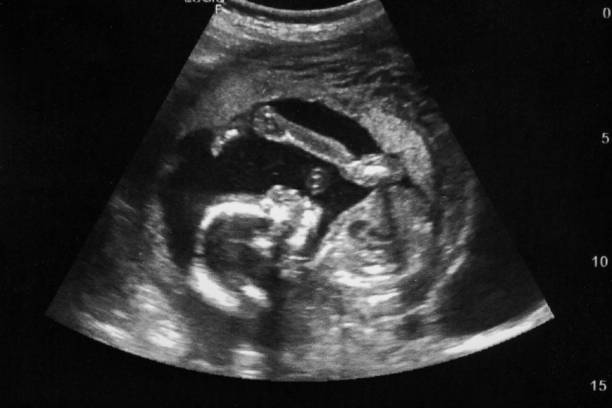

Ultrasound Service Updates

We are expanding our services in ultrasound to be able to offer select screening fetal echoes that meet the following criteria:

• Maternal issues:

• IVF pregnancy

• Preexisting diabetes

• Fetal issues:

• Family history of congenital heart disease

• Thickened NT from 3-6 mm (anything over 6 mm needs SLC only)

New visit type - Fetal Echo Doppler

EPIC Order-Fetal Echo Doppler (select performing dept of MBMC or COH7)